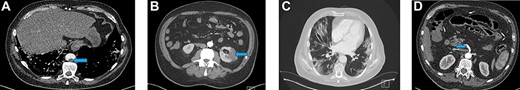

Blood investigations showed an elevated white blood cell count (WCC), a low lymphocyte count and elevated C-reactive protein (CRP). The thrombin time was prolonged (Table 1). A computed tomography (CT)—angiogram of lower limbs showed complete thrombosis of the infrarenal aorta, the common and external iliac arteries bilaterally, the left common, proximal superficial and profunda femoral arteries (Fig. 1A). A CT scan of the chest showed patchy and ground-glass shadowing predominantly in the bilateral lower lung lobes (Fig. 1B). A throat swab was positive for COVID-19.

(A) A CT scan of the chest showed patchy and ground-glass shadowing predominantly in the bilateral lower lung lobes. (B) CT-thorax showing pulmonary changes. (C) CT-angiogram demonstrating aorta and left CIA patency with residual thrombus in right CIA post-operatively (blue arrow)

A repeat CT-angiogram was performed. It confirmed that much of thrombus within the distal aorta and left common iliac arteries had been successfully removed; there was still a 25 mm occlusion in the proximal segment of the right common iliac artery with distal flow (Fig. 1C).